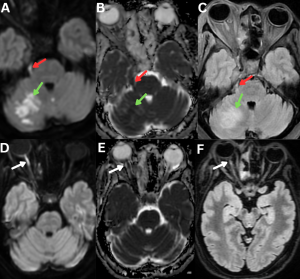

Fig 11: Clinical history:

A 55-year-old diabetic male presented with facial numbness, visual blurring, and acute-onset gait imbalance.

Figures A–C:

Axial diffusion-weighted imaging (DWI), apparent diffusion coefficient (ADC), and FLAIR images demonstrate diffusion restriction with corresponding T2/FLAIR hyperintensity involving the right trigeminal nerve (red arrows), consistent with trigeminal neuritis. Additionally, acute infarcts are noted in the right cerebellar hemisphere, showing DWI hyperintensity with corresponding ADC hypointensity and FLAIR hyperintensity (green arrows).

Figures D–F:

Axial DWI, ADC, and FLAIR images demonstrate diffusion restriction with associated T2/FLAIR hyperintensity involving the right optic nerve (white arrows), consistent with optic neuritis.